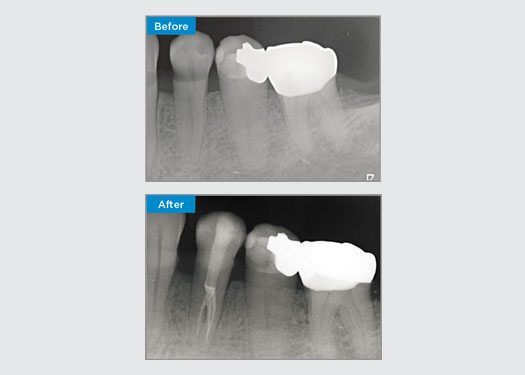

El paciente presentó pulpitis irreversible en la pieza dental 46. A partir de la radiografía preoperatoria, la pieza dental 46 se presenta con una raíz distal adicional (morfología dental Radix Entromolaris). Una escaneo CBCT ha confirmado la presencia de raíz distolingual con curvatura grave de la raíz. Una cuidadosa selección de limas es fundamental para esta raíz distobucal delicada.

Dr. Jack Lin, endodoncista, Sídney, NSW Australia

En esta situación, la preservación de la estructura del diente/raíz es esencial para reducir el riesgo de reborde, transporte, cierre, perforación y fractura de la raíz. La selección de casos, el diagnóstico y la planificación previa al tratamiento son importantes. La selección de limas de endodoncia con flexibilidad, eficiencia y respeto por la anatomía de la raíz natural es fundamental.